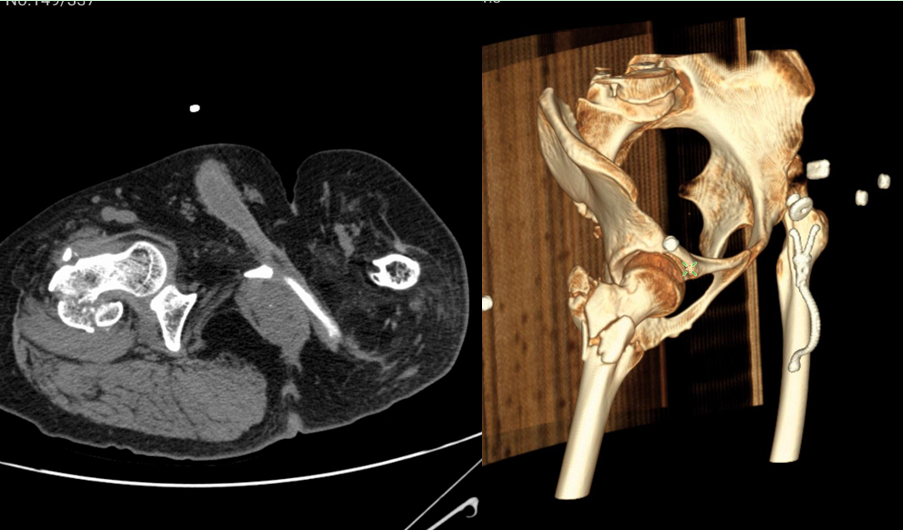

患者男 38歲

診斷:右股骨粗隆間骨折

手術方案:切開復位內固定術

輔助工具:3D打印病理模型

3D打印成型,1:1還原骨折部位各個骨塊的位置關系

手術模擬